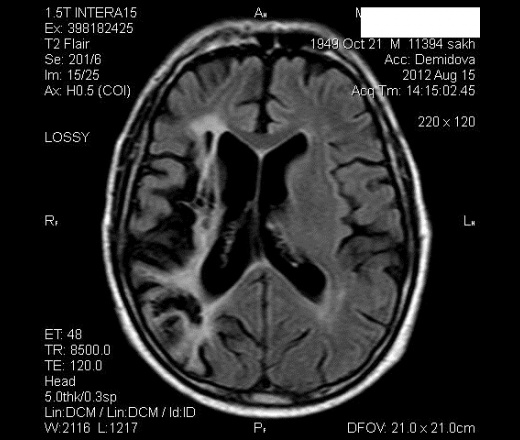

Валентин Львович, на представленном Вами снимке имеет место внутренняя гидроцефалия скорее окклюзионной или гиперпродуктивной природы, а не за счёт атрофии. Чистая атрофия (сенильная и алкогольная например) выглядит не совсем так опять же на мой взгляд..

Уверен, что в ближайшее время попадётся, сразу выложу. На самом деле гидроцефалия умеренно выраженная - как пневмосклероз в рентгенологии. Я однозначной точки зрения на эту .. патологию не имею. Если есть равномерное расширение субарахноидальгых пространств и борозд одновременно, в том числе и сильвиевых щелей - пишу наружную заместительную гидроцефалию. Если есть расширение вышеописанных пространств и желудочков - смешанную. Это что касается проявлений атрофии. Наверное мои знания устарели, буду читать. Бывают и варианты. Если расширены только желудочки как в выложенным Вами наблюдении) ставлю дополнительно тонкие сагитталы, поискать спайку в сильвиевом водопроводе, конечно если не расширен 4-й желудочек.

Вот типа так выглядит возрастная атрофия в моём понимании.

http://db.tt/8HBkbsd9 http://db.tt/u2hUAlxC http://db.tt/k1oq2pni Исследование целиком: http://db.tt/vGXeVFlR Извиняюсь за ссылки, с айпада файл изображения вставляется, но не появляется на странице. 2Helios :) Инициатива наказуема, просим расчертить желудочки и мозг на данном исследовании для вычисления индекса как пример. Кстати, мне не нравится основная пазуха у данной пациентки, но это к делу не относится.

Не могу скачать, не могу скачать.... Это наверно потому, что файл вчера в облако не ушёл целиком, а я комп аырубил :) сейчас поправил. А так вверху окна кнопка "download", нужно выбрать direct download. Вообще dropbox очень удобный сервис, я давно на него подсел. Насчёт пазухи- это не аплазия, на Т1 видно будет, я рекомендовал КТ. У данной пациентки могласно статье, приведённой Валентином Львовичем, "наружный тип ЦАП".